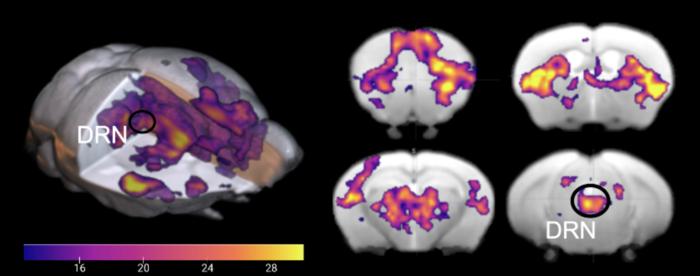

USING LIGHT STIMULATION AND MRI, SCIENTISTS COMPARED THE EFFECTS OF STIMULATING THE BRAIN’S SEROTONIN CENTER IN AWAKE AND ANESTHETIZED MICE, SHOWING A CLEAR DIFFERENCE IN ACTIVATION LEVELS BETWEEN THE TWO STATES.

They found that DRN serotonin stimulation causes activation of the cerebral cortex and the basal ganglia, brain areas involved in many cognitive functions. This result was very different from a previous study performed under anesthesia. Additionally, the brain's response to serotonin stimulation is strongly linked to the distribution of serotonin receptors (proteins activated by serotonin) and the connection patterns of DRN serotonin neurons.

“We clearly see from the high-field MRI images which areas in the brain are activated and deactivated during the awake state and under anesthesia when we activate serotonin neurons in the DRN,” Dr. Hamada said. “A previous study showed that the cerebral cortex and the basal ganglia were mostly deactivated under anesthesia, which we also observed, however, in awake states these areas are significantly activated.”

Activation of the brain when the DRN is stimulated in awake states

In awake states, when serotonin neurons in the dorsal raphe nucleus (DRN) are stimulated by light, specific areas of the brain are activated at different levels of intensity.